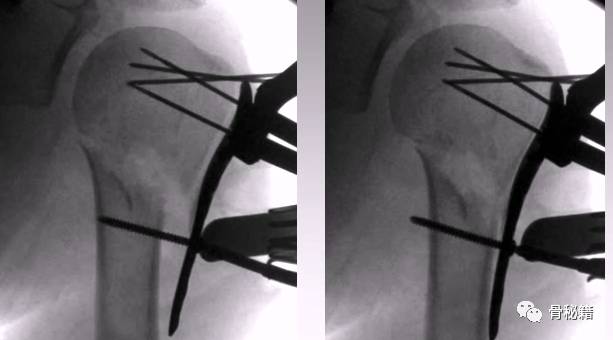

1、克氏针摇杆技术

正位的翘拨复位

腋位的翘拨复位